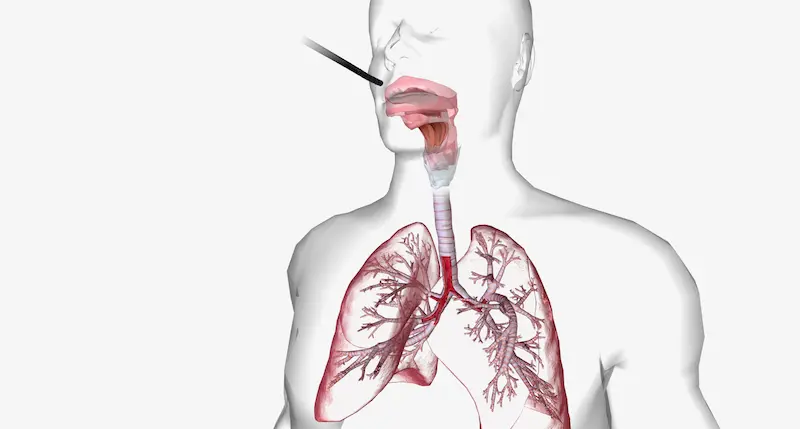

Бронхоскопическая биопсия — это малоинвазивная диагностическая процедура, которая позволяет врачу-пульмонологу или онкологу получить образец ткани (биоптат) из дыхательных путей или непосредственно из легкого для дальнейшего исследования. Ключевая цель — поставить точный диагноз при подозрении на различные заболевания, в первую очередь — рак легких. Процедура выполняется с помощью бронхоскопа, тонкой гибкой трубки с камерой и светом на конце. Проведение бронхоскопической биопсии в Турции гарантирует использование самого современного оборудования, что минимизирует дискомфорт для пациента и повышает точность диагностики.

Шаг 1: Подготовка и анестезия. Перед началом вам проведут местную анестезию горла и носа с помощью спрея, чтобы подавить кашлевой рефлекс. Для максимального комфорта и отсутствия неприятных ощущений бронхоскопия под наркозом или местной анестезией (чаще всего используется седация, или медикаментозный сон) является стандартной практикой. Вы будете спать и ничего не почувствуете.

Шаг 2: Введение бронхоскопа. Врач аккуратно вводит тонкий и гибкий бронхоскоп через нос или рот в дыхательные пути. Изображение с камеры передается на монитор, что позволяет детально осмотреть трахею и бронхи.

Шаг 3: Выполнение биопсии. Достигнув нужного участка, врач через специальный канал в бронхоскопе вводит миниатюрные инструменты (щипцы или иглу) и берет несколько крошечных образцов ткани. Этот этап абсолютно безболезненный.

Шаг 4: Завершение и наблюдение. После получения достаточного количества материала бронхоскоп извлекается. Вас переводят в палату для пробуждения, где вы проведете несколько часов под наблюдением медицинского персонала, чтобы убедиться в отсутствии осложнений. Полученные образцы немедленно отправляются на гистологический анализ.